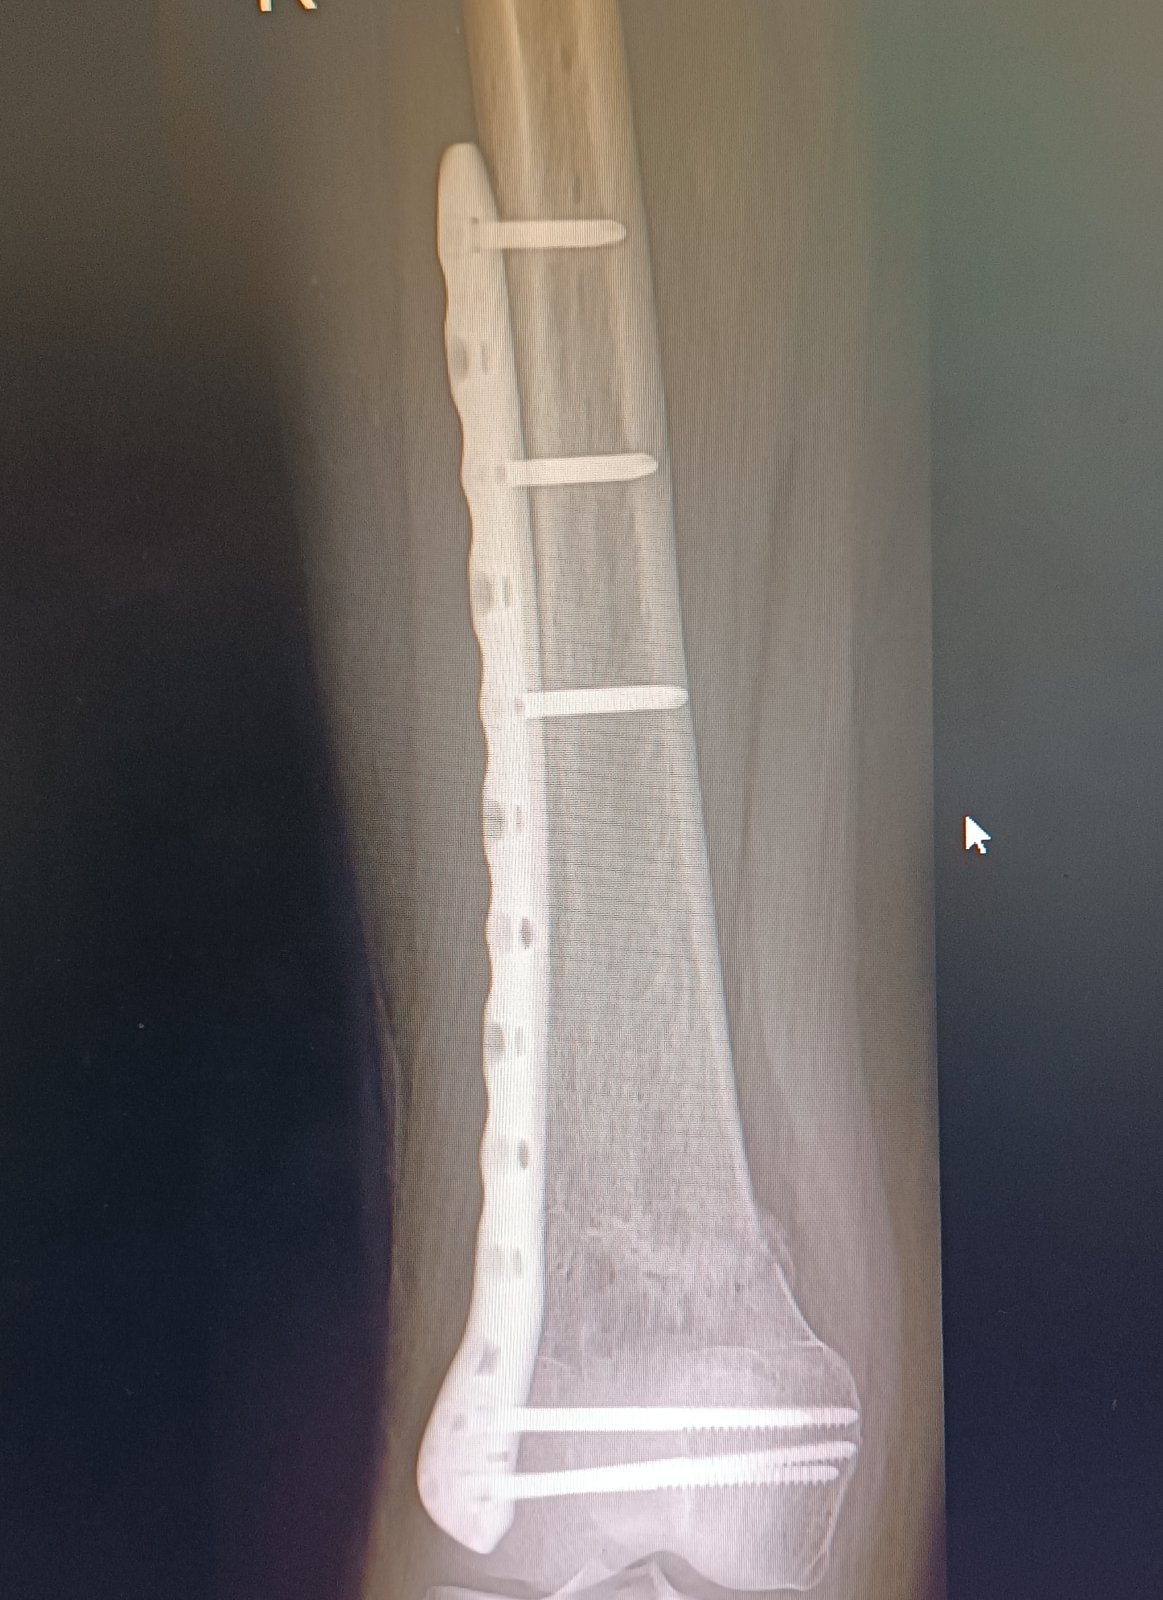

Dobrý deň ja mám platničku+ šroby v stehennej kosti ubehlo 14 mesiacov od operácie,mam naplánované vybraté teraz 30 apríla a som na prášky či do toho ísť alebo zrušiť 😞 názory lekarov niesu jednosmerné jeden bol za vybratie druhy načo ,primar na 60% ano na 40% nie mam 35 rokov dve male deti 2 r a 5r ešte som na rodičaku platnička mi nerobi nejake vyrazne problemy mam nohu len taku oťaženu v zime keď mrzlo ma pri dlho kracani bolelo koleno ale neviem či z platničky alebo zmena počasie 🥺 mam hrozný strach s tej operacie ta prva bola pre mňa trauma cele to čo sa mi stalo čo koľko bolestí som prežila a ty ľudia tam personal .. mám pocit že sa už zblaznim s toho každodenného rozmýšľania či to dať von alebo nechať plus mi na operáciu vychadza menštruácia takže cele zle poraďte ja viem že by som som sa skôr mala radiť s lekármi ale neviem už s akymi a skôr by som chcela počuť niekoho kto si tym vybratim prešiel 😢🙏